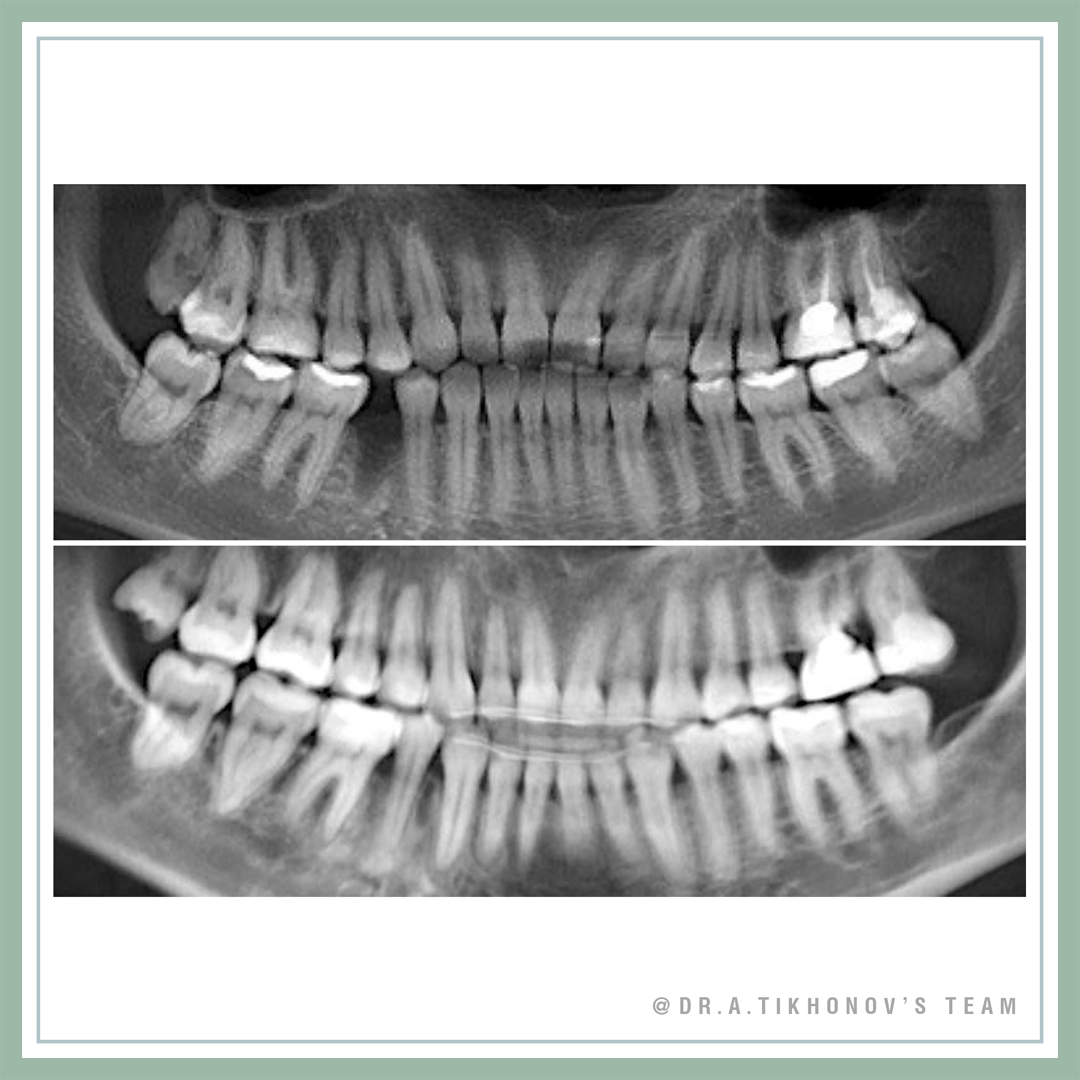

Коррекция арки улыбки и кривой Шпее интрузией с минивинтами

В современных реалиях, с наличием опыта и ортодонтических минивинтов, мы, конечно, решаем и параллельные задачи, старясь максимально улучшить эстетику улыбки наших пациентов. Минивинты применялись для внедрения 4, 5, 6 и выравнивания таким образом кривой Шпее.

Мы уже ранее обсуждали с вами в Блоге и регулярно разбираем на семинарах Школы ортодонтии и по минивинтам, что исправление Шпее в подобных случаях просто нивелированием без внедрения боковых, приведет к появлению десневой улыбки в переднем отделе, а также раскрытию прикуса из-за экструзии нижних боковых зубов. Внедрение боковых верхних зубов позволяет компенсировать этот побочный эффект, ну и конечно обеспечить естественную арку улыбки.

44 был удален уже до нас, поэтому промежуток закрывали с получением 3 класса по молярам.

Smile arc and curve of Spee correction by posterior intrusion with TADs. Gummy smile in posterior segments corrected. 44 was extracted before our treatment by another doctor, so we closed this space achieving class III molar relationship. Do not forget, that you can do it only if lower 8 is in the arch.